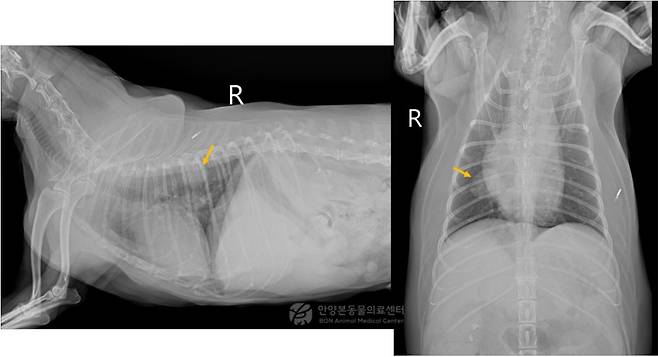

흉부 엑스레이 검사 결과 우측 폐 후엽 부위에서 약 2.5㎝ 크기의 연부조직 밀도 종괴가 확인됐다. 이후 보다 정확한 평가를 위해 CT(컴퓨터단층촬영) 검사를 시행한 결과, 동일 부위에 약 2.5㎝ 크기의 종괴가 확인됐다. 종괴는 인접한 폐혈관과 맞닿아 있고 일부는 흉막과 접촉하고 있었다.